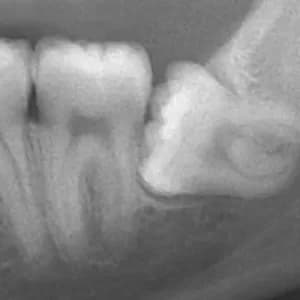

01. DIAGNÓSTICO

Evaluamos la complejidad del caso con examen clínico y radiografía panorámica 2D (el mismo día). Según la severidad, podemos solicitar un TAC 3D.

02. CIRUGÍA

Procedimiento rápido y seguro con anestesia local. La incisión es pequeña y, en la mayoría de los casos, toma pocos minutos.